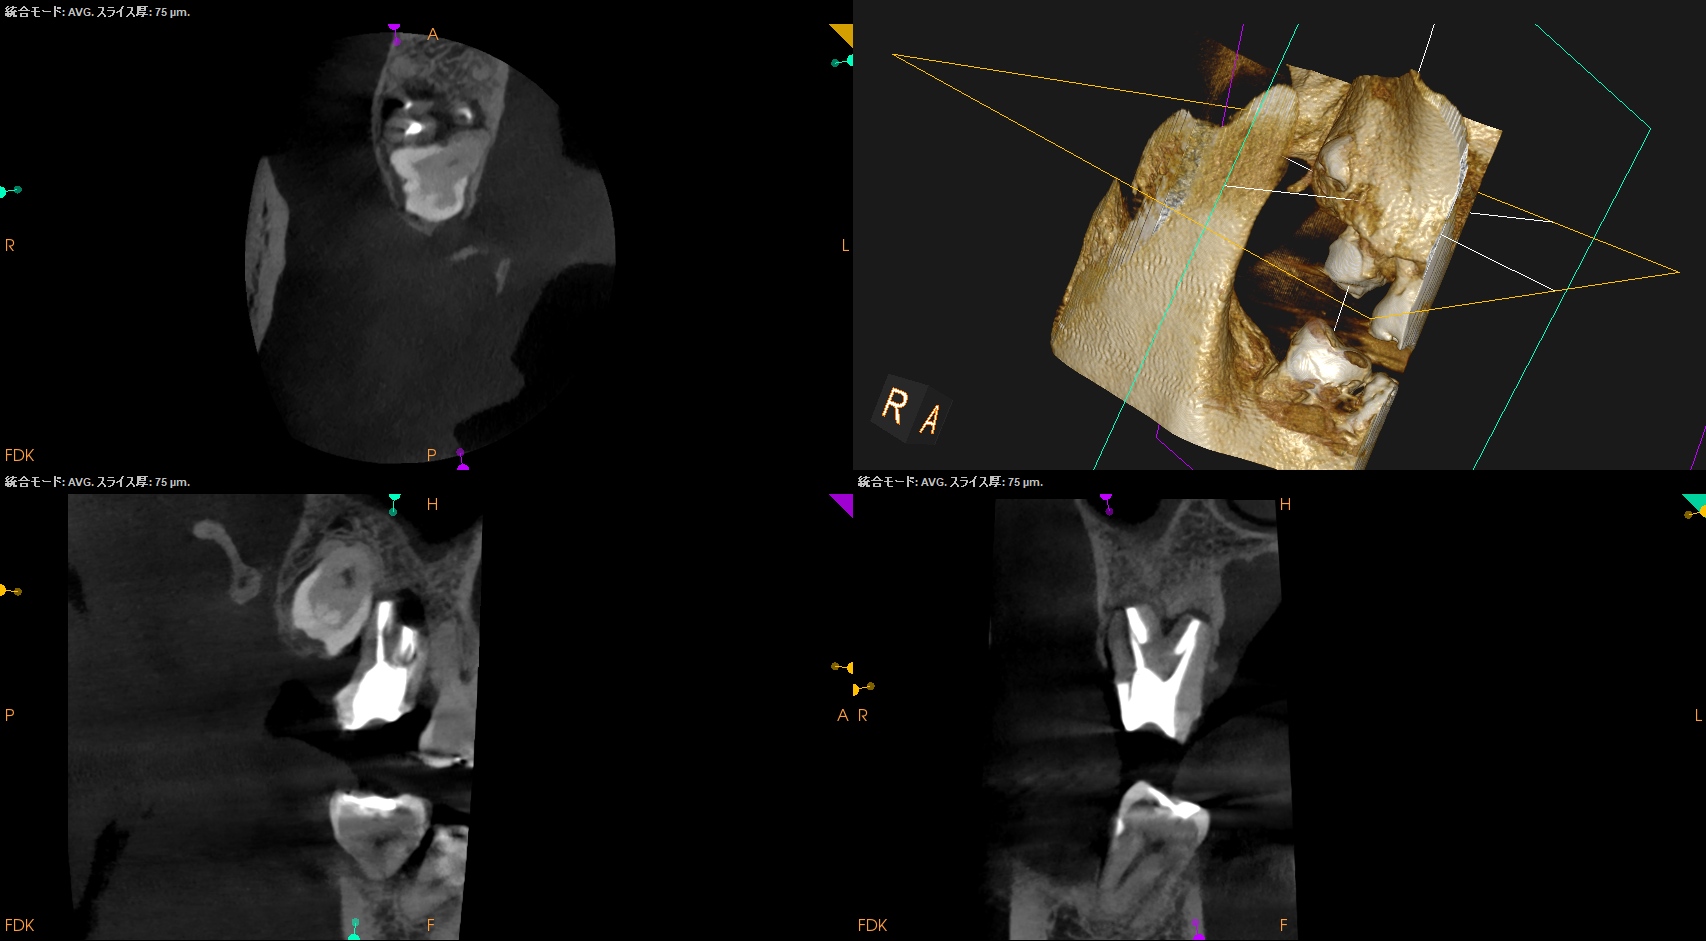

この後、歯牙の再植を試みようとするのだが…

なかなか再植ができない。

やはり脱臼+抜歯に時間がかかったからだ。

さて、このような時に我々はどうしたらいいだろうか?

☆Intentional Replantation時に再植行為が難しい場合の臨床的対応方法

1. Tooth Sloothで歯牙を患者さんに咬合させて元の位置に戻す

2. それでも再植が難しければ、抜歯窩の歯牙を再植する上でアンダーカットになっている部分(分岐部, 頬舌側・近遠心部分の歯牙のアンダーカット部分)の歯槽骨を除去する

すると抜歯窩へ戻すことができた。

術後にPAを撮影した。

MB

DB

P

問題はないだろう。